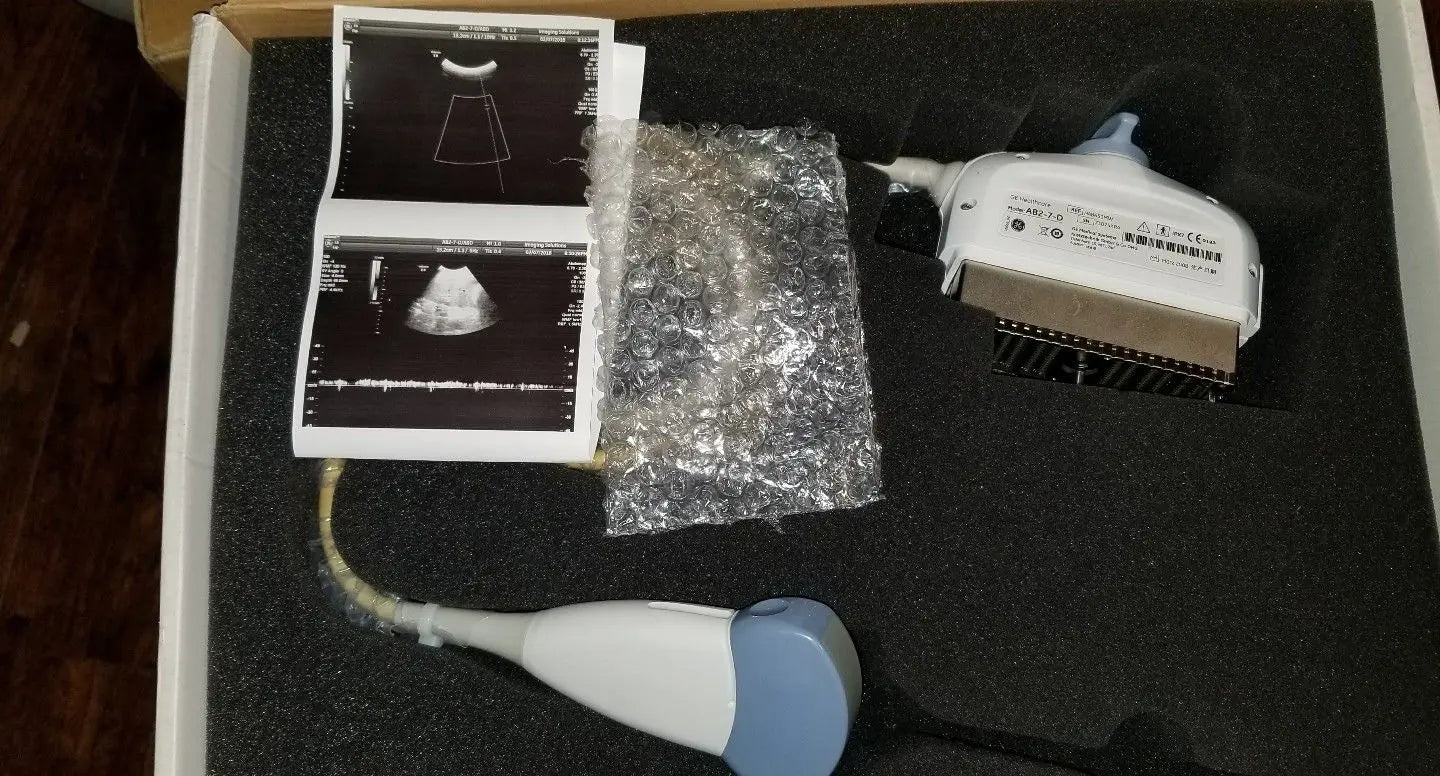

The GE AB2-7-D Ultrasound Probe: Elevating Diagnostic Imaging

Condition:

Brand: GE

Model: AB2-7-D

The GE ultrasound probe, model AB2-7-D, is renowned for its superior imaging capabilities. It features advanced transducer technology that provides high-definition images, which are crucial for accurate diagnoses. This probe excels in various medical applications, including obstetrics and gynecology, allowing medical professionals to visualize internal structures clearly. Because of its cutting-edge design, clinicians can rely on the GE ultrasound probe for precise assessments, enhancing patient outcomes significantly.

Comfort during ultrasound examinations is critical for both patients and operators. The GE AB2-7-D probe incorporates an ergonomic design that reduces strain during prolonged use. Its lightweight structure makes it easy to handle, allowing healthcare providers to perform detailed assessments without discomfort. Furthermore, the probe's smooth surface ensures patient comfort, which minimizes anxiety during examinations. This feature is essential because relaxed patients tend to yield more accurate imaging results.

Investing in the GE ultrasound probe means choosing durability and reliability. This transducer is built to withstand the rigors of a busy clinical environment, ensuring it remains functional over time. Regular calibration and maintenance are straightforward, which helps maintain its high performance. Additionally, the probe is compatible with a range of GE ultrasound systems, making it a versatile choice for many medical facilities. Therefore, healthcare providers can count on the AB2-7-D to deliver consistent performance day after day.